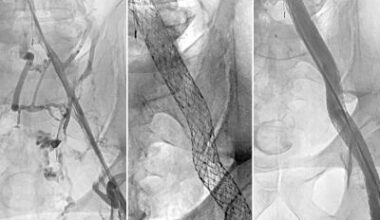

Simple stent procedure can treat post-thrombotic syndrome • healthcare-in-europe.com

Post-thrombotic syndrome […] has been undertreated, in part because there have not been evidence-based options available. This study…